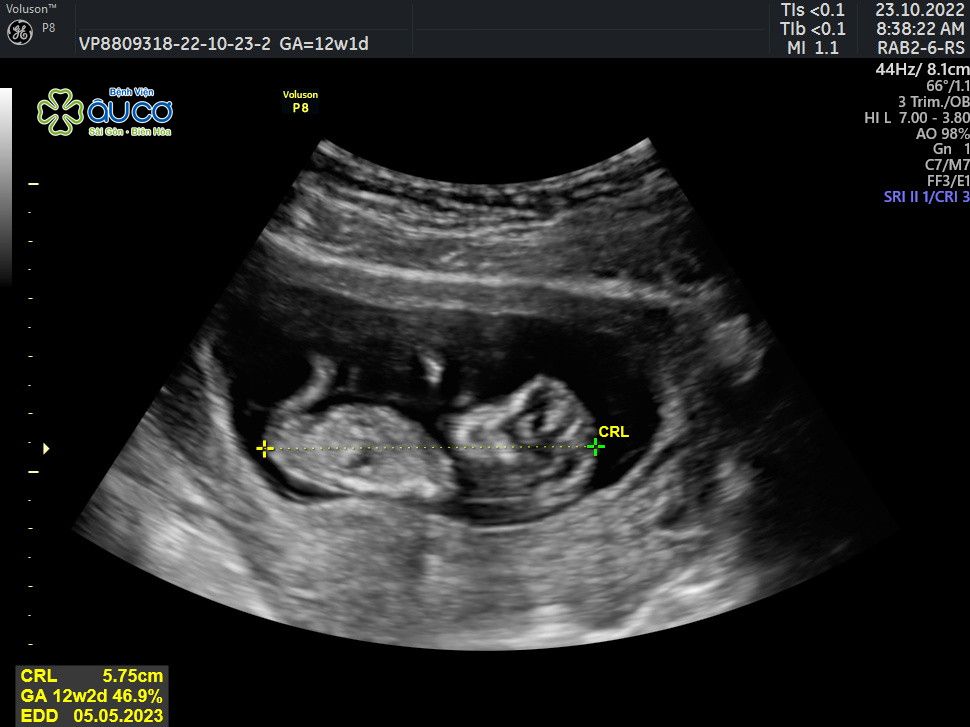

* Những hình ảnh siêu âm đáng yêu nhưng không kém phần nghịch ngợm của con qua các mốc thời gian:

| 12 tuần 1 ngày |

![[Chuỗi video] Địa chỉ đỏ Đồng Nai: Sân bay quân sự Lộc Ninh - địa điểm diễn ra những cuộc trao trả tù binh lịch sử](/file//e7837c02876411cd0187645a2551379f/042026/san_bay_loc_ninh.mp4.00_00_22_02.still001_20260425163845.jpg?width=400&height=-&type=resize)